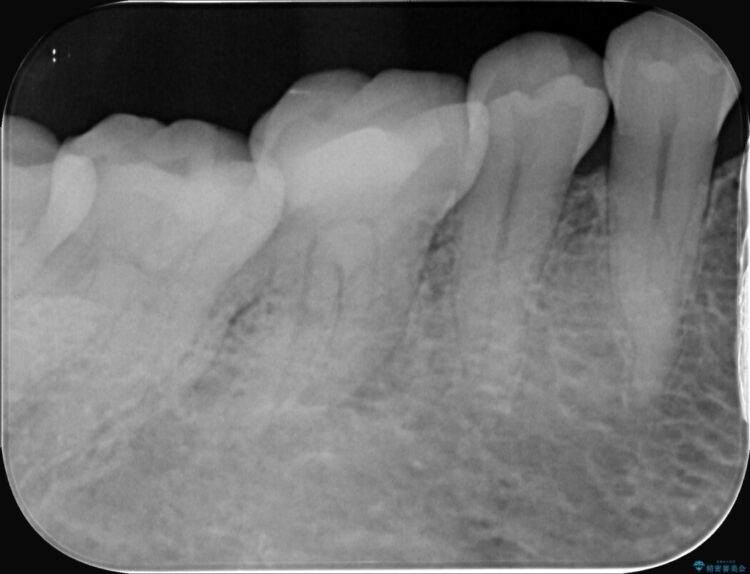

精密検査の結果、根の先に大きな病変が認められますが、根管内が狭窄し湾曲しているため、非常に難易度の高いケースです。

術後の経過は非常に良く、あんなに大きかった膿の袋は消え、健康な骨が再生しているのが確認できました。痛みや腫れも消えて抜歯を免れ、現在は被せ物を入れてしっかりお食事を楽しんでいただけるようになっています。